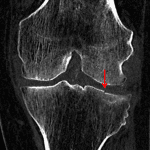

Indication: Knee injury

Findings

- Large lipohemarthrosis without acute fracture identified

- Mild tricompartmental degenerative changes

- Chondrocalcinosis of the menisci

- Vascular calcifications

- Surgical clips along the medial aspect of the distal femur and proximal tibia

Diagnosis

- Lipohemarthrosis

Large lipohemarthrosis without acute fracture identified. Recommend CT for further evaluation.

No joint malalignment.

Mild tricompartmental degenerative changes with chondrocalcinosis of the menisci.

Vascular calcifications.

Surgical clips along the medial aspect of the distal femur and proximal tibia.